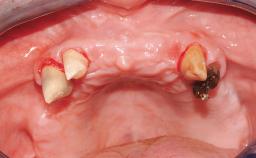

A 56-year-old female patient was referred to the clinic because of retention problems with her mandibular denture. She had been completely edentulous for more than 33 years and wore her sixth set of complete conventional dentures, which had been delivered 5 years previously. An oral surgeon had performed a vestibuloplasty in the interforaminal region of the mandible with a piece of skin tissue 12 years earlier. The panoramic radiograph and lateral cephalometric radiograph exhibited the hypotrophy of the inferior alveolar process. The mandible was a Cawood class VI,and the height of the mandible in the interforaminal zone was 15 mm.